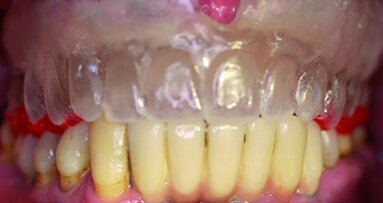

Le positionnement de l’implant est l’une des étapes les plus cruciales du traitement. L’emplacement précis est essentiel à la réussite d’une prothèse esthétique, phonétique, fonctionnelle et hygiénique. La plupart du temps, le positionnement de l’implant devrait être dans une limite de 0,5 mm (Figs. 1a–c). Il dépend de la précision de la mise en place du guide chirurgical et de l’exactitude du guide lui-même. Dans le cas du NobelGuide sur une arcade totalement édentée, un positionnement précis dépend de la capacité du patient à mordre de façon reproductible, d’une consistance et d’une épaisseur gingivale uniforme. De plus cela suppose que l’os ait un degré similaire de dureté pour les différentes vis de rétention. Malheureusement, comme le montre la revue de littérature de Schneider et al.6 et détaillé dans l’article publié par Valente et al.7, l’écart entre le point d’entrée et l’orientation diffère de façon quasi systématique entre la position prévue et celle effective des implants. Cela explique probablement certains échecs résultant de l’utilisation des guides en chirurgie fermée. D’autres facteurs d’échec peuvent être liés à une faible capacité de refroidissement lors du forage.8